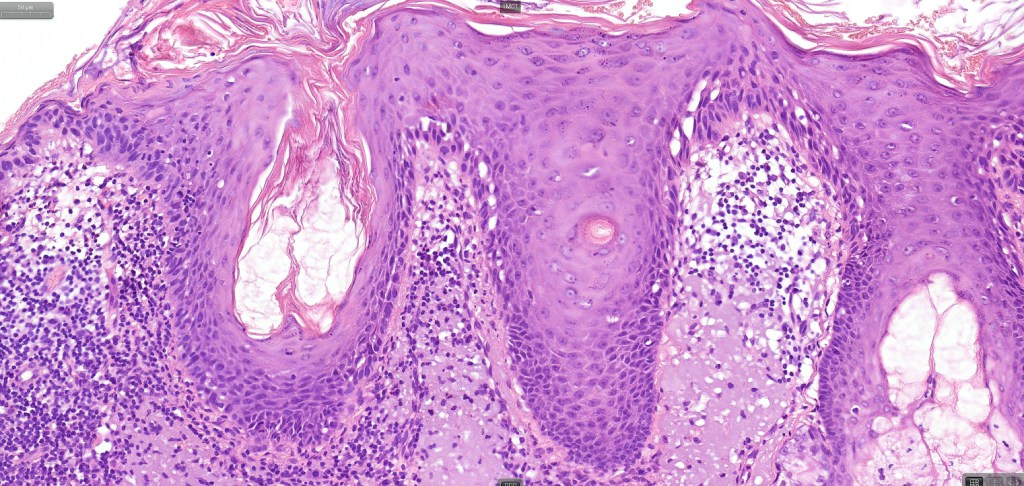

•Although a variety of subtypes are recognized, all are characterized by varying degrees of epidermal dysplasia

•Hyperkeratotic/hyperplastic actinic keratosis represents the prototype-alternating hyperkeratosis & parakeratosis- the former overlies the follicular & sweat duct ostia (Freudenthal funnel) while the latter overlies the interadnexal dysplastic epithelium & ranges from basal cell layer though to full thickness dysplasia (Bowenoid actinic keratosis); budding from the epidermis is a common finding; dysplastic epithelium commonly forms a mantle around the follicles and superficial sweat ducts

•Variable lack of maturation, nuclear irregularity, pleomorphism & mitotic activity